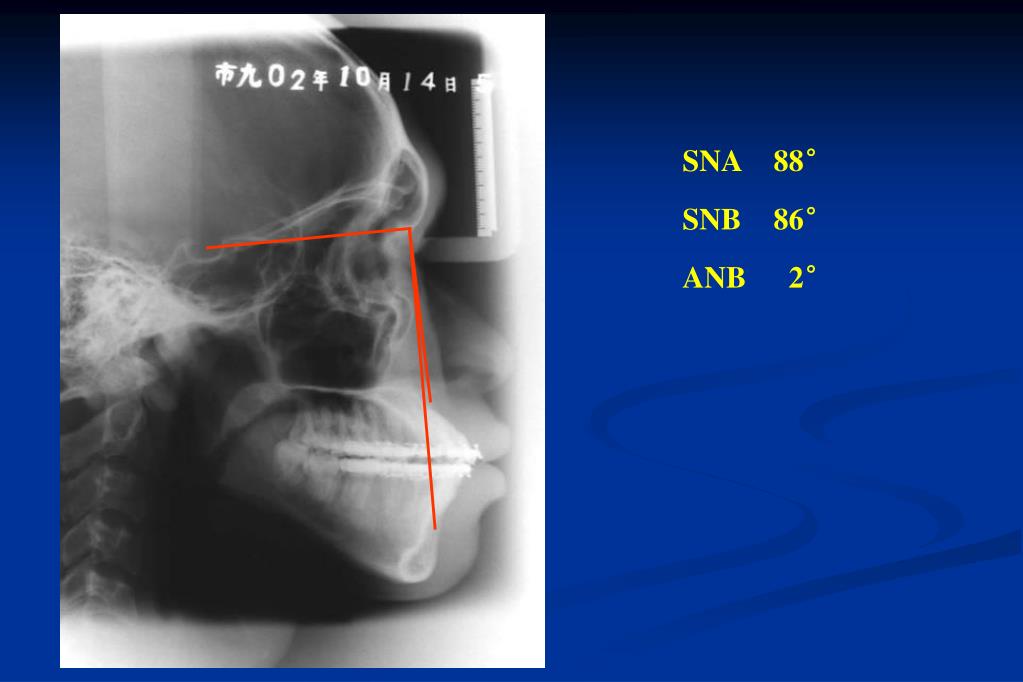

28. Post Sagittal Split Ramus Osteotomy

29. SNA 88° SNB 86° ANB 2°